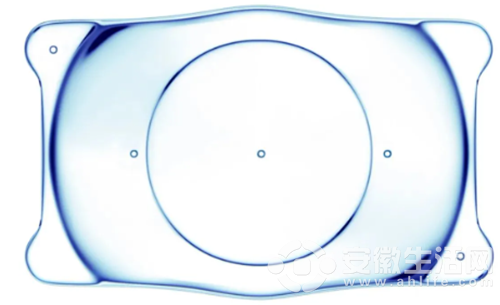

暑假假期選擇海島旅游 大部分人都是快樂得要飛起 而小王則因為一道海浪 差點灰暗到快心死 發生這一出悲劇的根源在于—— 玩太嗨 一不小心眼鏡被海浪拍丟了 丟失眼鏡后 高度近視的小王 走路、看東西都只能瞇著眼睛慢慢摸索 世界只剩下一片高糊的馬賽克 因為這場突如其來的意外 早就對近視手術蠢蠢欲動的小王 終于下定決心要 摘鏡 了!旅程一結束,小王就來到合肥華廈名人眼科醫院,找到了梁祖剛主任。在做完詳細的術前檢查后,劉才遠教授發現,小王左眼近視850度,右眼近視900度,屬于 高度近視 ,綜合評估其眼部情況,劉才遠教授向小王推薦了ICL晶體植入術。 ICL晶體植入術和激光類近視手術的區別 當前,近視手術主要分成激光類近視手術和晶體植入術。 激光類近視手術主要通過切削角膜,改變角膜曲率的方式來矯正視力,一般被稱為“減法”手術。不同激光類術式的矯正范圍不同,至高可矯正1200度的近視,但一般情況下,近視度數越高,需要切削的角膜厚度也就越多。 由于小王本身是高度近視,且角膜厚度偏薄,如果做激光類近視手術,術后無法保留住安全的角膜厚度,因此不建議做激光類近視手術。 ICL晶體植入術屬于近視手術的“加法”手術,主要是通過微創角膜切口將人工晶體植入眼內來矯正近視,無需削薄角膜組織,通俗來說,就等于在眼睛內植入了一副特殊的“隱形眼鏡”,可矯正1800度以內的近視、600度以內的散光。  晶體放入眼內會有異物感嗎?會移位嗎 ICL晶體植入術具備可逆,安全性高等優勢,放入眼內不會有異物感,且能收獲更高清的視覺效果,更好的夜間視力。 目前,全球只有一家生產ICL晶體的公司,位于瑞士,每一個ICL晶體都有一個專屬編碼。在術后檢查確認符合手術指征后,醫生會根據患者的眼部情況“量眼定制”晶體。 ICL手術所植入的晶體由具有良好生物相容性的材料制成,厚度僅50微米左右,比頭發的直徑還薄,能與眼睛融洽相處,不會產生排異反應,也不會有異物感。晶體植入后移位的概率極低,如若遇到嚴重的外傷或撞擊,導致晶體旋轉或移位,盡快就醫調整即可。  此外,高度近視患者無論是否做近視手術,都不建議進行強度大、危險性高、力量需求大的運動,比如蹦極、跳水、拳擊等劇烈運動。 聽完梁祖剛主任的介紹,小王仔細考慮后同意進行ICL晶體植入術。 經妥善安排后,梁祖剛主任為小王進行了ICL晶體植入術,手術順利完成。術后多次復查結果顯示,小王的雙眼眼壓正常,視力均已恢復至1.0。 看著重新找回自由“視”界的小王,梁祖剛主任不忘叮囑其術后注意事項,且一再強調要注意愛護眼睛。 梁祖剛主任表示,很多人存在“近視手術可以治愈近視”的誤區,但在目前醫療技術條件下,近視一旦發生不可治愈,近視矯正手術并非一勞永逸地治愈了近視,而僅是通過手術改變了眼睛的屈光狀態,讓近視者不用戴眼鏡也能看得清。 因此,做完近視手術后,還是應該注意保持良好的用眼習慣,避免過度用眼。此外,高度近視患者較普通近視患者發生眼病并發癥的風險更高,建議其至少每年檢查一次眼底。  合肥華廈名人眼科醫院屈光手術科由梁祖剛業務副院長領銜,配備德國蔡司全飛秒精準 4.0-VISULYZE、 波前像差檢查系統、三維眼前節分析儀等眼科設備。 科室開展角膜激光和晶體植入類多種近視矯正手術。可矯正近視(50~3000度),散光(50~600度),遠視(600度以下)等屈光不正問題及老視。此外,還可以對一些復雜的治療性屈光問題提供優質的解決方案,如角膜移植術后的屈光不正、白內障術后殘留的屈光不正等。 實行六大質量控制體系,對近視手術的檢查、醫生、設備、技術、流程和服務進行一系列的把關和改進,通過需求分析、術前檢查、數據采集、手術實施、術后護理等流程, 根據每位患者差異化的眼部條件和用眼需求“最眼” 定制、 提供更優質的個性化解決方案。并依托華廈眼科醫院集團各地近 100 家眼科診療機構,近視手術術后可實現全國華廈異地復查。  責任編輯: 許吳百